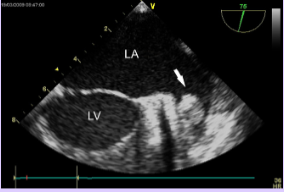

Rhabdomyoma

What is seen in this TTE?